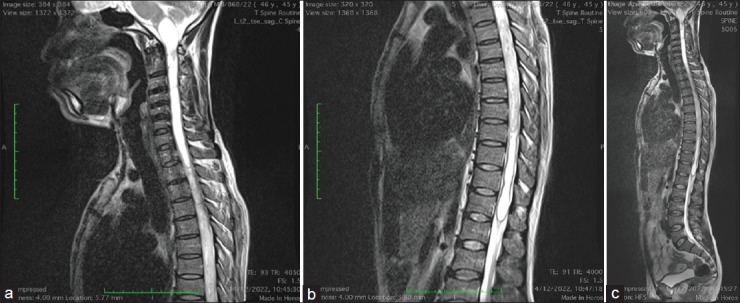

The shunting system has been generally recognized for the treatment of syringomyelia. However, recent publication has documented the role of atlantoaxial stabilization in the treatment of this condition. The objective is to present a case report highlighting our experience in the management of syringobulbia and syringomyelia in an adult male. We present a 45-year-old male who presented with an inability to walk with associated bladder and bowel symptoms. Neuroradiological studies of the brain and the whole spine revealed an extensive syringomyelia extending from the medulla oblongata to the T12 thoracic spinal level. There was no obvious focal mass lesion or bony lesion, and there were no anatomic features suggestive of Chiari I malformation. A management decision was challenging in this case. Atlantoaxial stabilization was considered based on Atul Goel's philosophy that the basic pathology in syringomyelia is C1/C2 instability, and that treatment is C1-C2 fixation. Intraoperative findings confirmed atlantoaxial instability from the direct bone handling during the procedure. There was immediate postoperative improvement in his motor function, which remained sustained, with free and brisk active mobilization at 3 months follow-up. Neuroimaging performed at 14 month's postsurgery revealed a reduction in the size of the syrinx cavity. This single and first experience of atlantoaxial stabilization for the treatment of syringomyelia in our environment may support the assertion by Goel that atlantoaxial instability is the pathology in syringomyelia, and atlantoaxial fixation should be a therapeutic consideration.